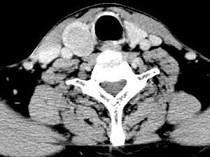

问题 男,43岁,右颈部扪及一包块,CT如图所示,应诊断为 ( )

选项 A、甲状腺原发淋巴瘤 B、甲状腺转移癌 C、甲状腺腺癌 D、结节性甲状腺肿 E、甲状腺腺瘤

答案 E